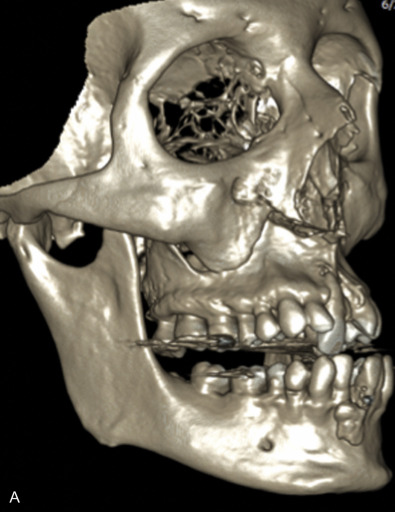

The gold standard for radiographic evaluation is thin-slice helical computed tomography (CT). Midface fractures are confirmed by axial, coronal, and sagittal views. The degree of comminution, bone loss, and detailed images of the fracture patterns can be assessed and juxtaposed to surrounding soft tissue structures. 3D reconstruction, when utilized, can aid in visualizing the complex 3D anatomical orientation of fracture fragments that occur in Le Fort injuries and facilitate reconstructive planning.

Le Fort III fractures generally consist of a combination of fractures that involve the palatine bones, the maxilla, the pterygoid plates, the nasal bones, lacrimal bone, and zygomas; they essentially separate the face along the base of the skull. The fracture pattern extends through the nasofrontal suture along the medial wall of the orbit, through the inferior orbital fissure and the lateral orbital wall to the zygomaticofrontal suture. In addition, the zygomaticotemporal suture is separated. The fracture extends across the sphenoid bone resulting in dysjunction at the pterygoid plates ( Figs. 1.13.16 and 1.13.17 ). The septum is separated from the cribriform plate of the ethmoid. Pure Le Fort III fractures are rare, and in actuality, most are ZMC fractures in conjunction with Le Fort I and II fractures lending the appearance of a comminuted “Le Fort III.” The force is delivered from the orbital level, resulting in craniofacial dysjunction. The fracture is generally more comminuted and more extensive on the side of force application.